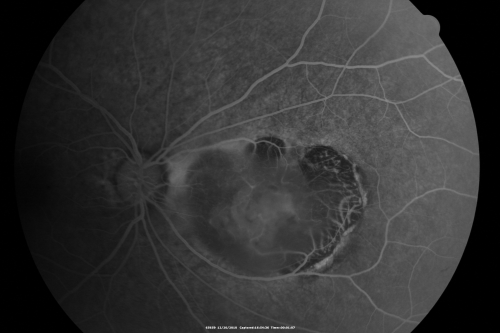

Retinocytoma - Retinoma - Regressed Retinoblastoma 43 year old male incidental finding

Retinocytoma - Regressed Retinoblastoma - Retinoma